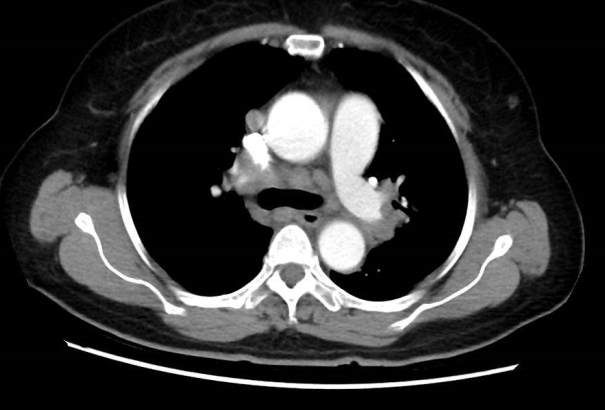

62岁的陈阿姨,因持续一个月的胸闷和呼吸困难入院。胸部CT扫描显示,她的右侧锁骨区、纵隔和双肺门有多发性肿大的淋巴结,这可能是淋巴瘤或结节病的迹象。

诊断结果:肺结节病

通过EBUS技术,医生能够在实时超声引导下,精确定位淋巴结并进行穿刺活检。通过这种方法的优势在于EBUS-TBNA的阳性率超过90%,能够有效区分良性和恶性病变。同时减少了对患者的创伤,避免了传统外科手术的风险。实时超声能够即时评估样本质量,确保获取足够的组织进行病理分析。